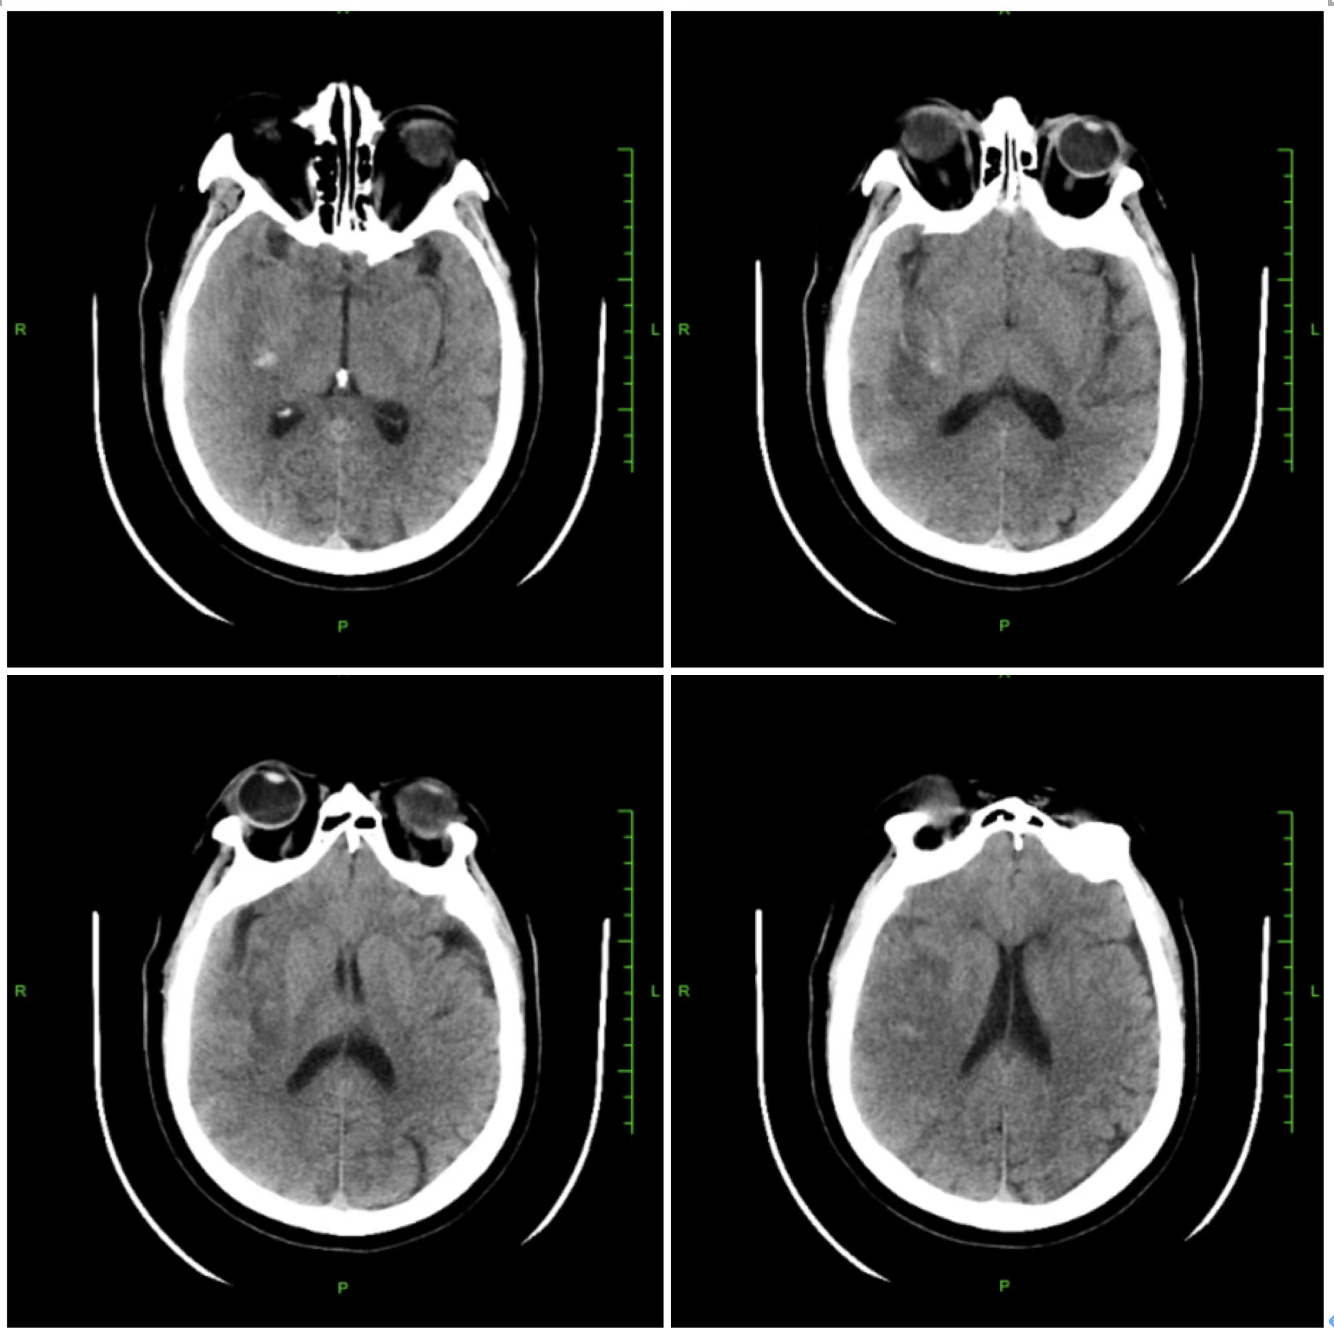

术前影像学检查结果:急诊头颅CT:可见右侧大脑中动脉高密度征,右侧半球未见明显出血及低密度影;头颅DWI:右侧颞叶大面积脑梗死。

7、术后情况:术后12小时,患者凝视消失,语言流畅,左侧肢体肌力恢复至3级,头颅CT复查:右侧颞叶无症状少量出血灶,散在低密度影。次日,左侧肢体肌力恢复至4级。